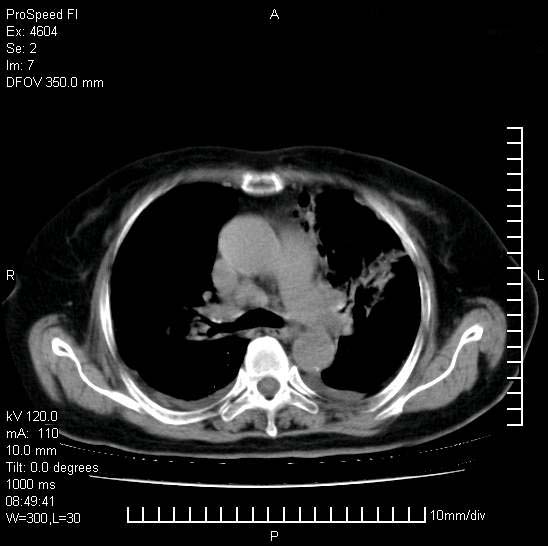

标题: CT15528:女性,79岁,近几日晚上高热,39度,仍咳少量血 [打印本页]

十几年前曾患肺结核,一周前突咳血约100ml,中性粒细胞稍高,诊断两上肺陈旧结核,下肺炎症,给予抗炎治疗,近几日晚上高热,39度,仍咳少量血,4天前ct及今天ct上传。

[face=黑体]8月30日[/face]

支持陈旧性肺结核并两下肺感染,两侧胸腔积液。

考虑1双肺tb灶;右下肺支气管壁增后,建议除外占位 3双侧胸腔积液,

短短几天内,病变范围明显增多扩大,以左侧明显,而且双侧出现胸水,还是考虑感染.

支持  结核ban感染,节段性肺不张,支气管内膜结核可能

短短几天内,病变范围明显增多扩大,以左侧明显,而且双侧出现胸水,我更多考虑左侧中心性肺癌并并阻塞性不张及肺炎,炎症变化也太快了!

1)两肺结核并感染。2)不排除左肺上叶中央型肺癌并阻塞性肺炎、肺不张可能;建议行纤支镜检查。3)右肺门及纵隔淋巴结肿大。4)双侧胸腔积液。

陈旧性肺结核及左下肺不张,咯血后肺部感染,双胸腔积液,高热可能与痰液引流不畅有关。